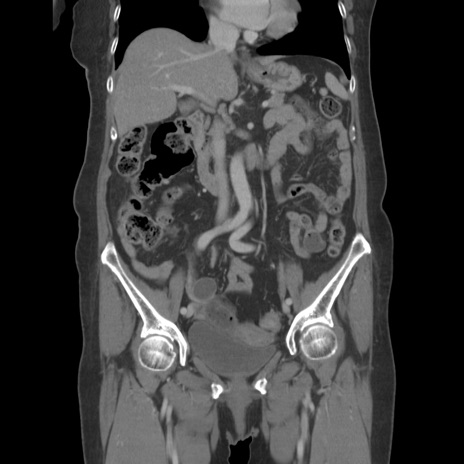

横断像

【症例】80歳代女性

【主訴】下腹部痛

【現病歴】約8時間前より下腹部痛の出現あり、救急外来受診。

【既往歴】両側付属器切除

【身体所見】意識清明、下腹部正中に手術痕あり、その部位に一致して圧痛と反跳痛あり。腸蠕動音は亢進。

【データ】WBC 9300、CRP 0.15